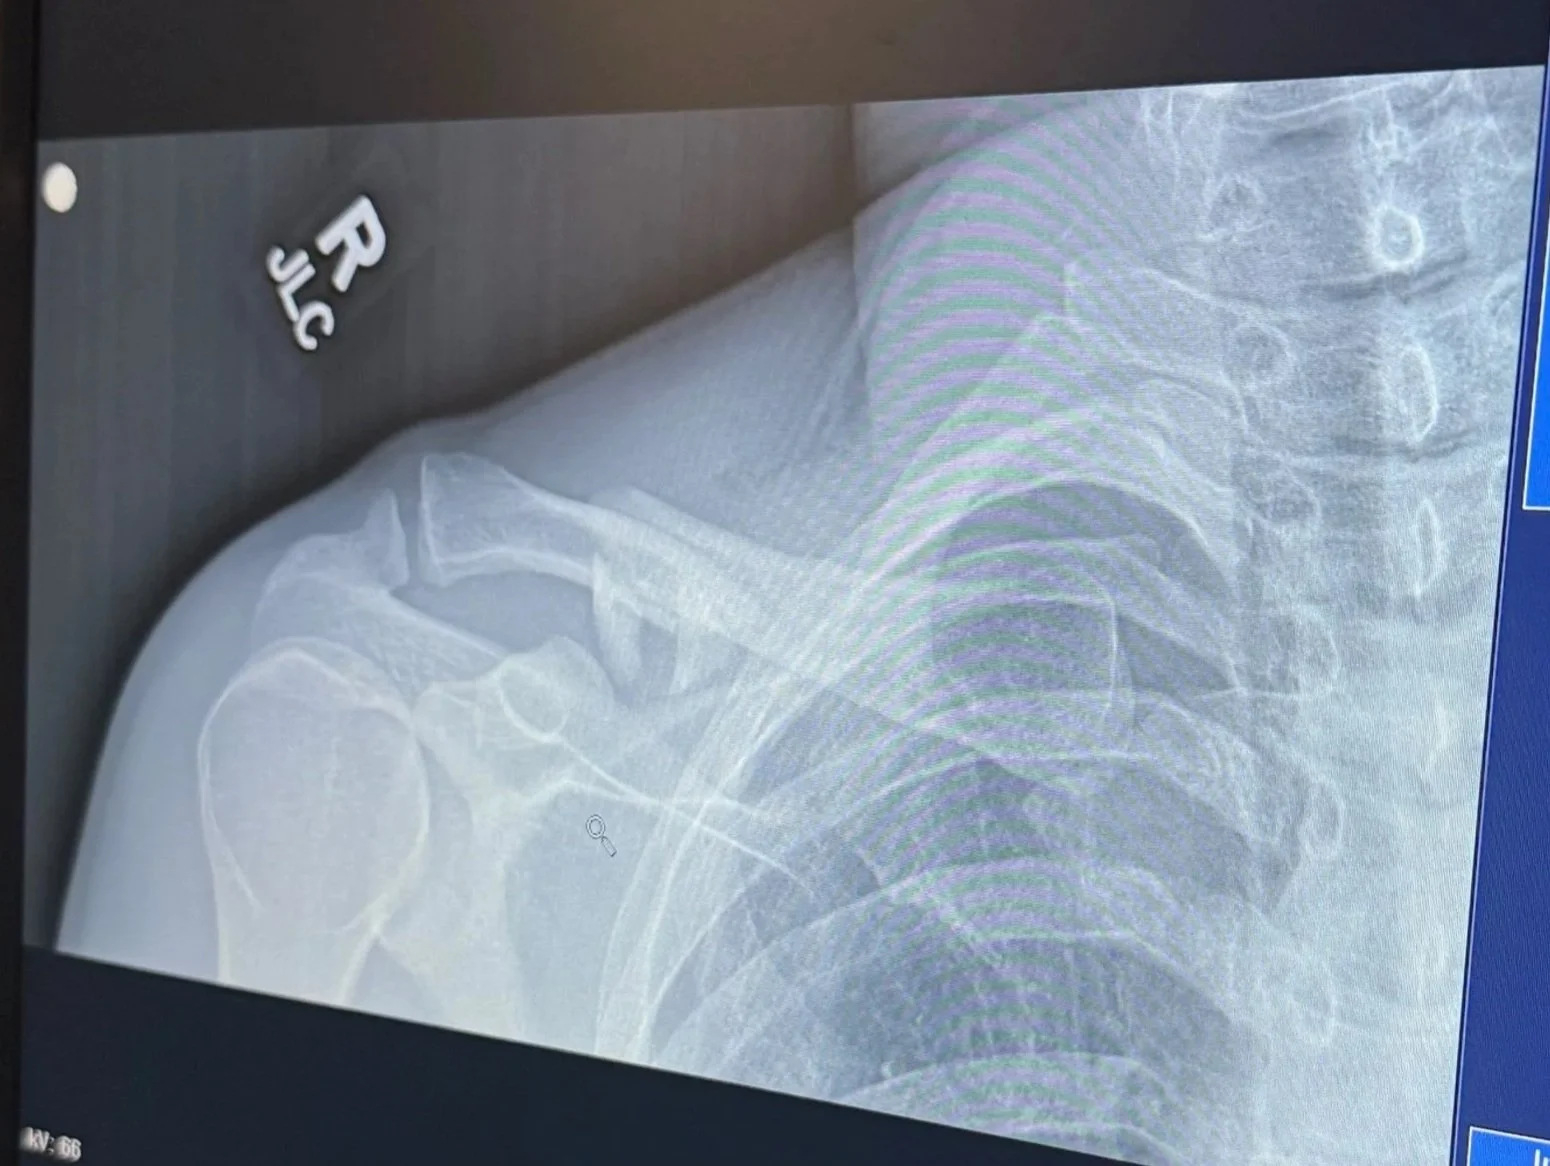

After the other riders assessed the situation and my condition, we started taking action. One of the riders with me, Charlie, fashioned a sling/splint out of my hand saw from my backpack and some rope he had in his pack. Brian road ahead to pick the best path forward to get back down to a vehicle. Fortunately where we were at only required about a half mile walk to the trail head. As we walked I found it hard to breath and just chalked it up to anxiety or adrenaline. I’d later learn that this was because of three broken ribs and a partially collapsed lung. Another rider in our group, Brock, was able to drive me back into town where we met up with my wife then headed to the hospital to get x-rays and make a surgery plan.

In the hospital it became apparent that the doctors and nurses cared less about my collar bone pushing my skin up and more concerned about my lung. After a CT scan we learned that my right lung was collapsed at the top and then partially down by a couple of the rib fractures, in total a little over 10%. This is good news because I later learned that at 15% they go in with a chest tube. At this point they admitted me and for the first time in my life I had to spend the night in the hospital hooked up to an IV, heart monitors and everything else. The hospital is serious stuff, they come in about every hour to poke you with a needle or fill you full of pills, then in the morning have the audacity to ask you how you slept. They liked me so much, they decided to keep me another night to make sure my lung would improve. I finally got release about noon on Tuesday, 41 hours after my arrival.